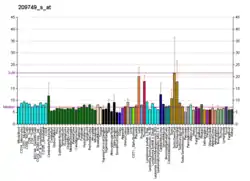

The rs1799752 I/D polymorphism consists of either an insertion (I) or absence (D) of a 287 base pair alanine sequence in intron 16 of the gene.[24] The DD genotype is associated with higher plasma levels of the ACE protein, the DI genotype with intermediate levels, and II with lower levels.[24] During physical exercise, due to higher levels of the ACE for D-allele carriers, hence higher capacity to produce angiotensin II, the blood pressure will increase sooner than for I-allele carriers. This results in a lower maximal heart rate and lower maximum oxygen uptake (VO2max). Therefore, D-allele carriers have a 10% increased risk of cardiovascular diseases. Furthermore, the D-allele is associated with a greater increase in left ventricular growth in response to training compared to the I-allele.[27] On the other hand, I-allele carriers usually show an increased maximal heart rate due to lower ACE levels, higher maximum oxygen uptake and therefore show an enhanced endurance performance.[27] The I allele is found with increased frequency in elite distance runners, rowers and cyclists. Short distance swimmers show an increased frequency of the D-allele, since their discipline relies more on strength than endurance.[28][29]